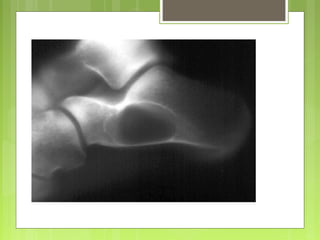

Condroblastoma

- Menos del 1% de los tumores óseos primarios

- 2ª década con predominio en varones (2/1).

- La mayoría cerca de la rodilla, predilección

por la epífisis. Menos frecuentemente en la

pelvis y costillas.

- Dolorosos, por su localización próxima a las

articulaciones producen derrames que

limitan la movilidad articular.